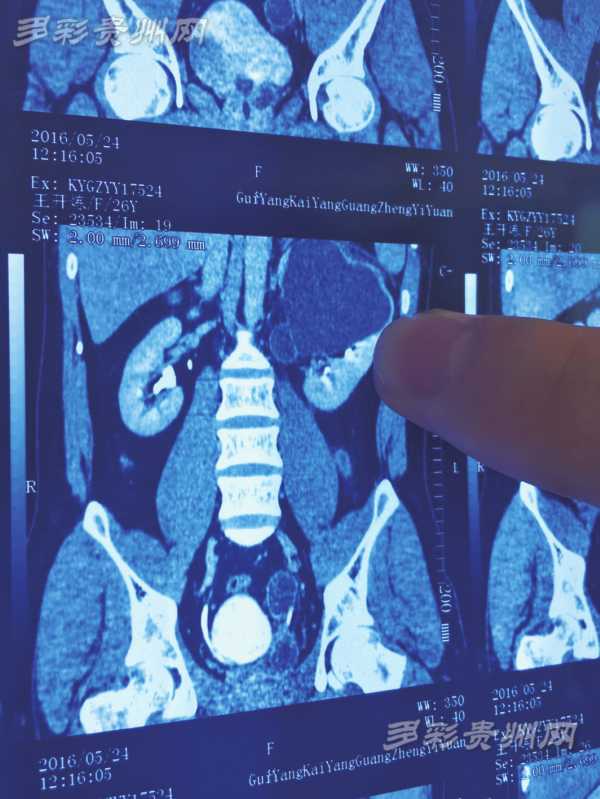

影像检查 资料显示,王开炼有4个肾,黑色阴影部分就是感染的左上肾。右边的两个肾在这份资料上已经重叠,看起来并不明显。

5月中旬,王开炼被送入贵阳宝山北路的一家三甲医院治疗,经过确诊,王开炼患的是重复肾。“这时我的病情已经很严重了,每天打4针止痛针都不管用。”最后,王开炼选择转院。5月24日,王开炼被送进贵阳市金阳医院泌尿外科,当天被安排住进6号病床。“经过CT、磁共振和泌尿系造影检查,发现他确实长有4个肾,是比较罕见的重复肾。”贵阳市金阳医院泌尿外科学术技术带头人、苏州大学在读医学博士梅傲冰介绍,作为王开炼的主治医生,已有20多年泌尿医学经验的他,也是第一次遇到4个重复肾的病例。

梅傲冰拿出王开炼的检查资料向记者介绍:“他的左上肾患有严重的肾积水,覆盖压迫左下肾,合并感染导致腰疼、发烧等一系列病症。”原来,王开炼4个肾每侧两个,各有一个供血系统和排尿系统,每侧的两个肾类似连体婴儿一样长在一起。“正常人的肾跟自己的拳头大小差不多,王开炼的4个肾都比正常人小,只有婴儿拳头那么大。”梅傲冰说,4个肾中,左下肾相对较小,只有正常人的三分之一那么大。

而出现病灶的肾,则是左上肾,里面有大量的积液。根据影像检查结果,积液已致这个肾变得比原来大3至5倍。“如果不及时切除左上肾,他的合并感染会更加严重,且还可能会危及到其它的肾。”梅傲冰说,好在经过半个月的治疗,王开炼的感染控制住了。在此期间,梅傲冰多次研究了手术切除方案,最后决定用最先进,也是最成熟的腹腔镜微创手术切除左上肾。